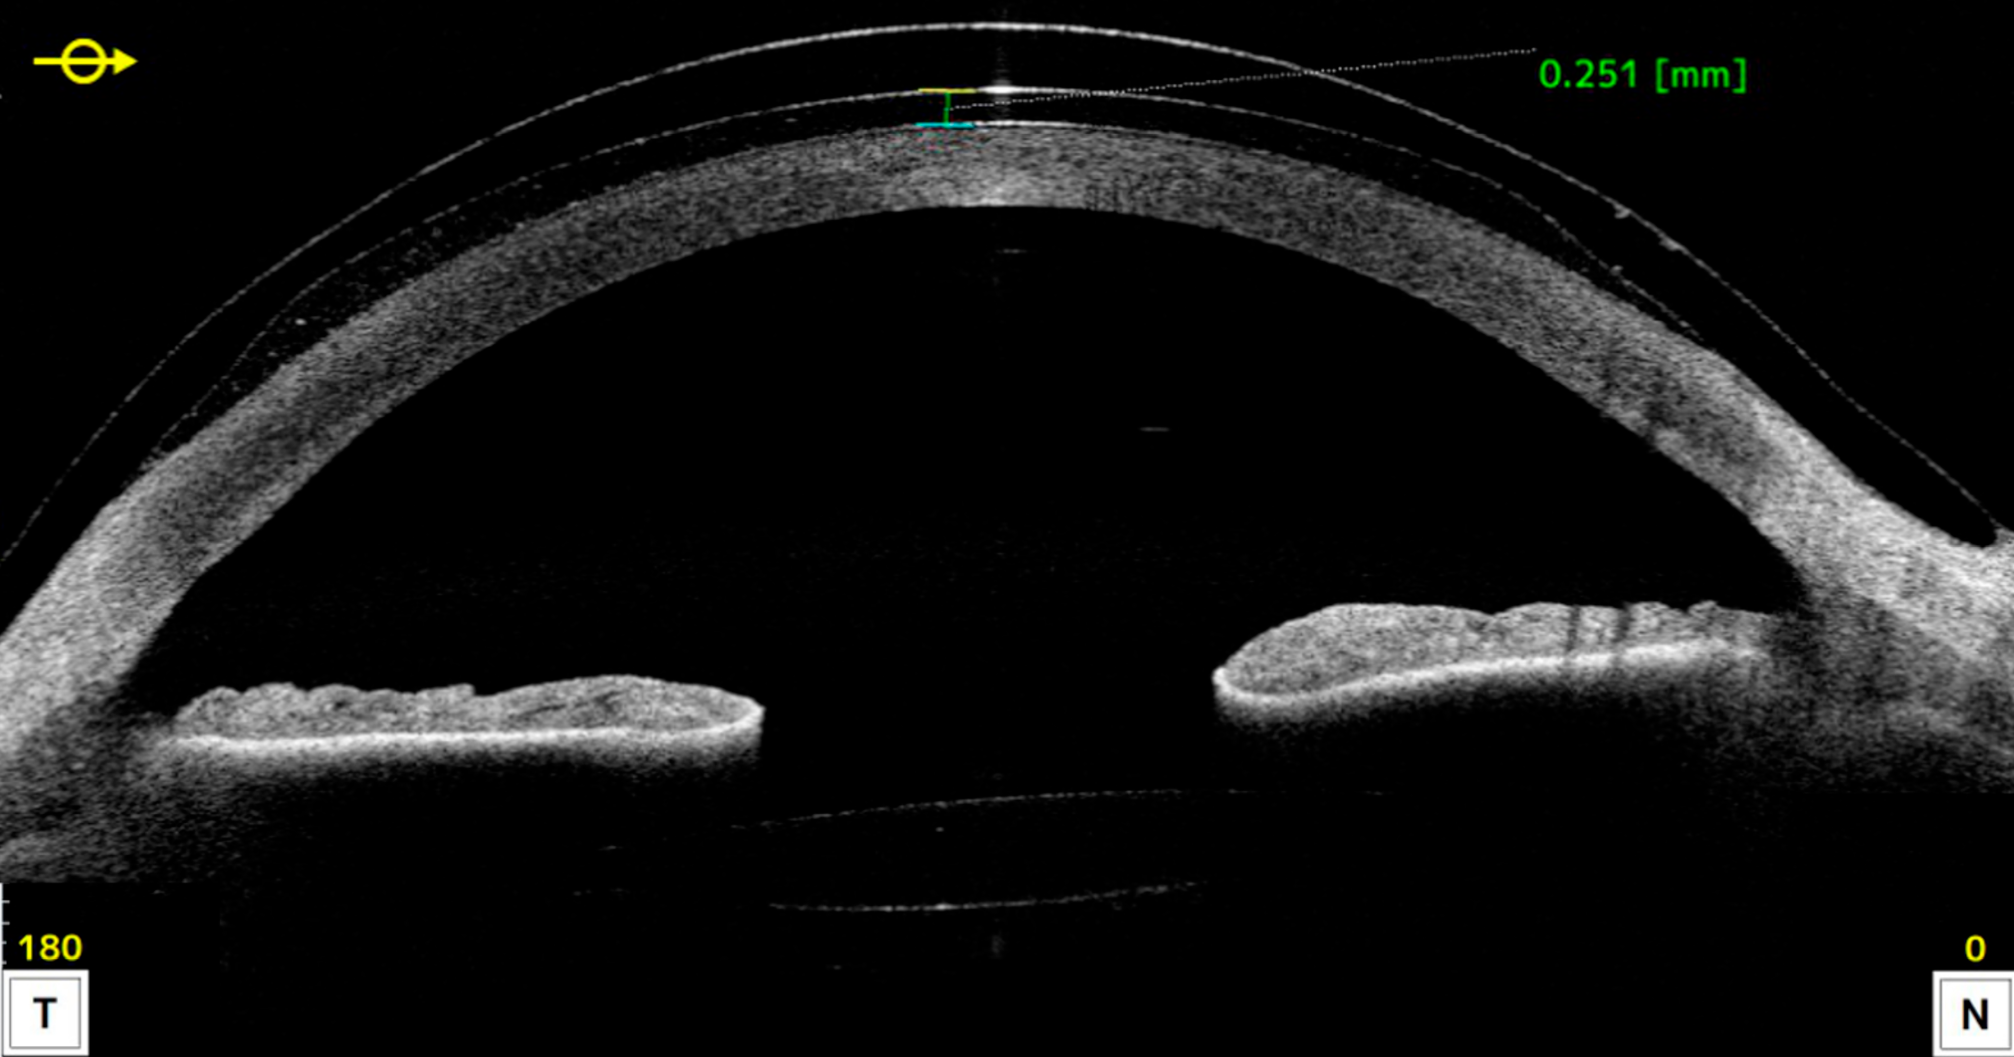

Figure 2. Spectral Domain OCT (Optovue RTVue-100® ; Optovue Inc®, Fremont, Californie, États-Unis).

A. Œil droit et B. Œil gauche : dépôts hyperréflectifs dans l’épithélium, le stroma antérieur et moyen.